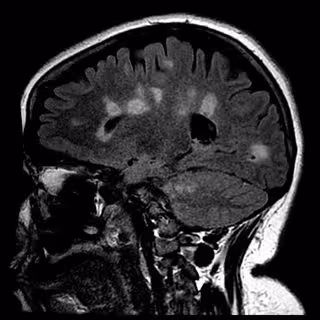

Cicatrización del cerebro en la esclerosis múltiple

Los pacientes en ambos grupos informaron de mejoras ligeras pero iguales un año más adelante. Se emplearon imágenes de resonancia magnética (MRI, por sus siglas en inglés) de sus cerebros para contabilizar el número de nuevas lesiones en su mielina y los investigadores no encontraron diferencia después de seis meses y tras un año entre el grupo de tratamiento y el del simulacro.